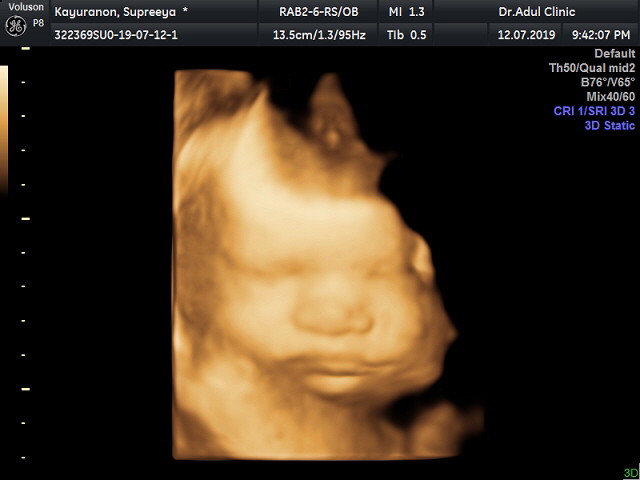

32 weeks คร้าฟๆๆ นู๋ชื่อบีลิฟ